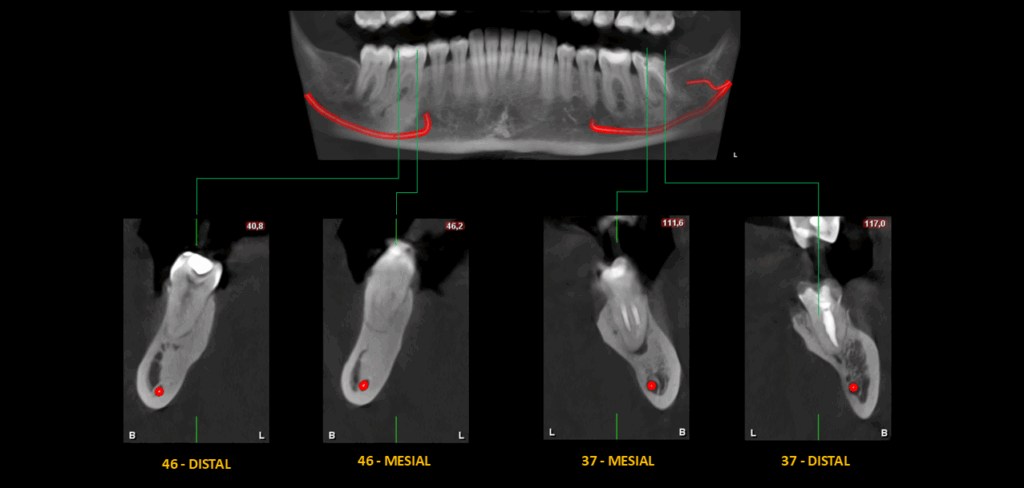

En la radiografía panorámica se evidencian múltiples restauraciones coronarias. En relación con la pieza 37, se observa tratamiento endodóntico, proceso osteolítico periapical en la raíz mesial y un aumento de la densidad ósea circundante que se extiende hasta la cortical superior del conducto dentario inferior. Con respecto a la pieza 46, se observa una restauración coronaria extensa, un ensanchamiento del espacio para el ligamento periodontal periapical y un aumento de la densidad ósea periapical que se extiende hasta el conducto dentario inferior.

En el estudio complementario mediante tomografía computarizada de haz cónico (TCHC), se observa la obturación subextendida de conductos en la raíz mesial de la pieza 37, se confirma el proceso osteolítico periapical y el aumento de la densidad ósea circundante con extensión hacia el conducto dentario inferior. En la pieza 46 se observa una restauración oclusal hiperdensa con material restaurador isodenso subyacente próximo a cámara pulpar y se corrobora el aumento de la densidad ósea periapical que además se extiende hacia la tabla ósea lingual.

CORTES TANGENCIALES

- Osteítis condensante en piezas 37 y 46.